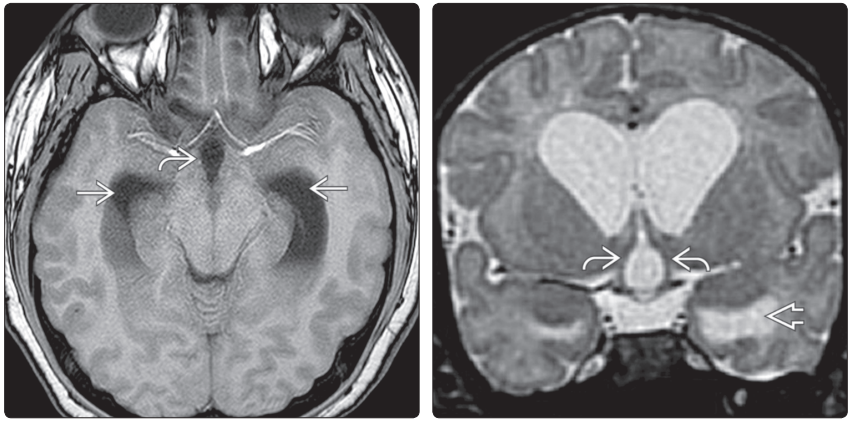

(左图)第三、第四脑室MR矢状中线位T1WI示:第三脑室视交叉隐窝→、漏斗隐窝↪、松果体上隐窝⇒,形态正常;中脑导水管→,正常情况下其近端窄于远端;第四脑室的尖顶(fastigium)和Magendie 孔↪,矢状中线位显示好。(右图)MR横断位T1WI示(侧脑室前角和三角区水平):包括细长的枕角在内的侧脑室正常形态

(左图)MR冠状位T;WI示(侧脑室体部→和枕角水平↪):颞角呈裂隙状,位于海马内侧喙缘(rostralto the medial aspects of the hippocampi)。(右图)冠状位FLAIR MRI示:正常儿童三脑室↪,呈裂隙状。正常额角→狭窄,双侧稍欠对称。颞叶内侧高信号⇒显示的是胚胎性颗角的正常残余